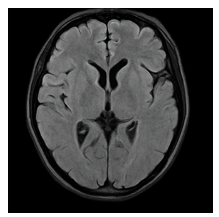

A 9-month-old infant was brought to our hospital by her mother, who noted that the child doesn’t look at her or respond to her calls. The prenatal history was normal; she was born at term with a birth weight of 2.8 kg, but there was a delay in the birth cry and a 5-day NICU stay due to hypoxia during delivery. The infant was diagnosed with developmental delay, as she achieved head control at six months but had not yet sat or crawled. She also didn’t reach for objects, typically expected by six months. An MRI showed periventricular leukomalacia due to hypoxic ischemic encephalopathy (Figure 1). Visual testing revealed her acuity at 20/2000, but she responded positively to the Hiding Heidi low-contrast face test. The child’s gaze was downturned, and she could not follow objects or reach for them; however, her anterior and posterior segment of eye was normal, and her refractive error was mild at +2.00 diopter. We diagnosed her with Cortical Visual Impairment (CVI) and referred her for vision therapy.

Figure 1 An MRI showed periventricular leukomalacia due to hypoxic ischemic encephalopathy.